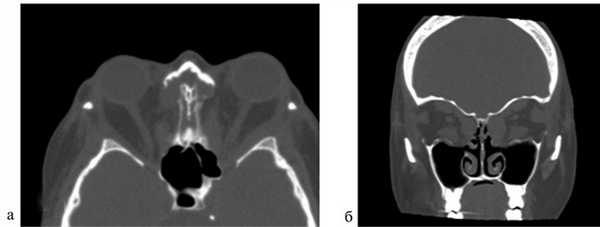

Величина экзофтальма до операции составила 25±2,3 мм (от 21 до 30 мм). В результате сбалансированной декомпрессии орбиты было выявлено достоверное уменьшение экзофтальма в среднем на 4,8 мм (от 4 до 9 мм), его величина в среднем составила 20,2±1,9 мм (рис. 3 и 4).

Рис. 4. Компьютерная томография после операции: аксиальный срез (а); фронтальный срез (б). Видны сформированные костные окна.